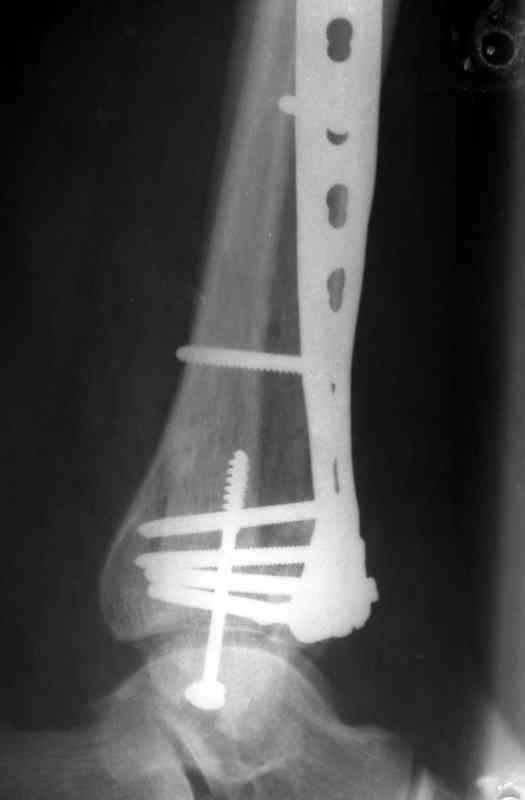

Кстати, при переломах переднего края по классификации АО В-3 при переломах пилона пластина укладывается по передней поверхности. Она достаточно тонкая и эластичная, не надо этого бояться. Посылаю три снимка.

На рентгенограммах типичный перелом пилона по типу С-3. есть опыт до 100 открытых опреаций у нас в клинике. 20 примерно в год. Принцип один -все внутрисуставные переломы нуждаются в открытой репозиции и внутренней стабильной фиксации. При поступлении КТ не надо, так как получается только нагромождение костей. Истинной картины нет. Главное восстановить длину малоберцовой кости - это ключ к успеху. При поступлении меньше всего надо думать о сосудистых расстройствах, т.к. сама операция и репозиция даже сначала частичная даёт улучшение сосудитых нарушений. Причём очень быстро. Операция в 2этапа. При поступлении доступ позади наружной лодыжки, причём обязательно. После этого репозиция малоберцовой кости и фиксация пластиной 1/3 трубки под винт 3,5. Дренаж и любой аппарат наружной фиксации. Затем после спадения отёка на 5-7-10 день аппрат снимается и дугообразный разрез спереди от медиальной лодыжки 10-12 см. Главной чтобы расстояние между 1 и вторым разрезом было не меньше 7-8 см. Тогда не будет некрозов лоскутов. Таранная кость используется как матрица на неё укладываются отломки и фиксируются пицами. Ренг-контроль. Отломки лежат все отдельно, но ничего не высыпется. При переломах С-3 всегда нужна костная пластика (из крыла). Фиксация пластиной лист клевера простой или LCP. Гипс не нужен. Дренаж до 48 часов. Операция длится 3-4 часа обязательно без жгута. Посылаю примерно такой же случай.